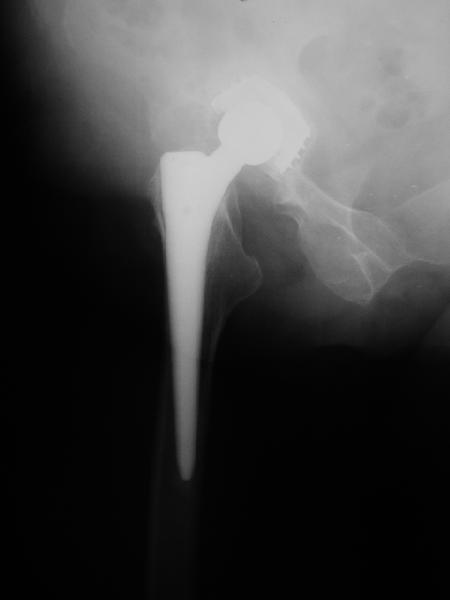

24 апреля 2005 г. правый сустав профиль (тут и болит)

Простите-не заметил последнего приложения.Не вижу рентгенологических признаков loosening.Так что изотопы могли бы и помочь

На представленных Р-граммах явных признаков нестабильности эндопротеза нет. Чашка хоть и медиализирована, но стоит так же, как и 3 года назад и остеолиза нет. Есть остеолиз вокруг проксималного отдела ножки, но линия тонкая и не захватывает дистальный отдел. Судя по клинике, можно думать о травме (отрыв) ягодичных мышц в

2. Судя по рентгенограммам явной нестабильности тазового ибедренного компонентов не видно, но это не решает проблемы. Гематома? - пунктируйте - не инфекция ли? Посев пунктата нужен. 3. Не спешите - погодите по времени - возможно имеет место банальная травма в области искусственного сустава с гематомой - все пройдет. Ревизия только при убеждении в нестабильности компонентов сустава или при инфекции, что пока не манифестирует. Еще раз - не спешите, не горит. С уважением и с праздником. А Рыков Хабаровка.